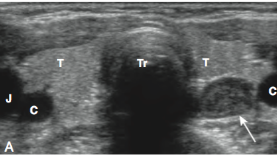

• *Hypoechoic solid lesion**

• Homogeneous

• Oval (~1cm)

• *Hypervascular**

• Arch

• Feeding vessel

• Differentials:*

• Lymph node*

• Thyroid nodule*